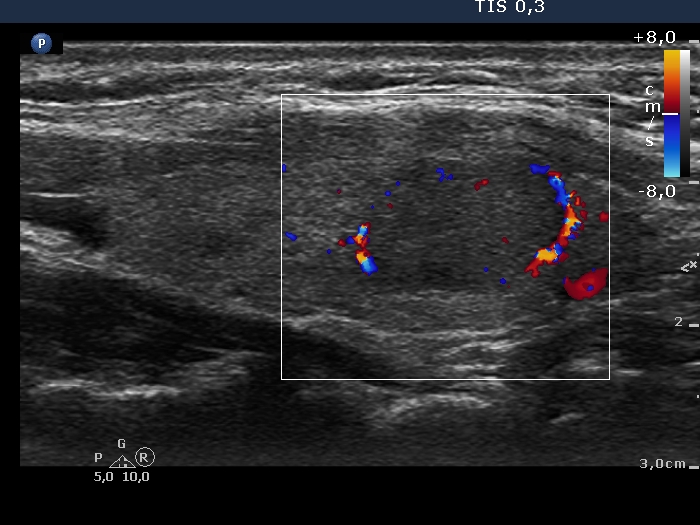

100 consecutive cases of papillary cancer - case 089 (ultrasonographic picture 6)

Follow-up examination a year later

Left lobe, transverse scan, color Doppler mode. The lesion has perinodular vascularity.